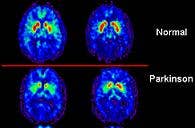

Marios Politis from Imperial College London spear headed the research to determine the causes of side affects to fetal-tissue transplants. He and his colleagues performed PET scans on the brains of patients who had received fetal cells 13 to 16 years ago and showed signs of dyskinesia. The scans showed increase serotonin activity in the brain. The ratio of serotonin neurons to dopamine neurons had increased dramatically. Politis and his team also studied how a serotonin inhibitor (5-HT1A or BuSpar) affected the uncontrolled movements. That medication greatly decreased the signs of dyskinesia, but only temporarily and without noticeable improvements in their scores on motor control tests. Still, the drug's effect is rather incredible to see. There are videos of the patients after treatment which can't be embedded here, but you can find them on the Science Translational Medicine website.

[image credit: WikiCommons, Politis et al, STM 2010]